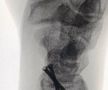

Calvarul prin care a trecut Lance Stroll pentru a lua startul în prima cursă de Formula 1 » Operat de urgență cu 12 zile înainte